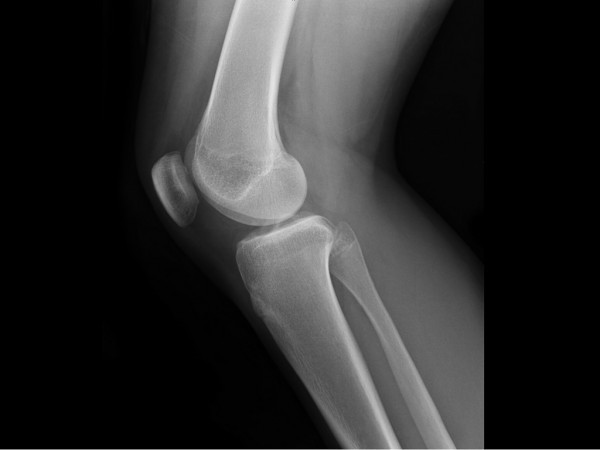

يُعرَّف الغضروف (بالإنجليزية: Cartilage) على أنَّه نوع من النسيج الضام الموجود في الجسم، ومن الجدير بالذكر أنّ الغضروف يُعدّ نوعاً من الأنسجة الفريدة؛ لأنّه لا يحتوي على أوعية دموية أو أعصاب، وبدلاً من ذلك تتميّز خلايا الغضروف المعروفة باسم الخلايا الغضروفية (بالإنجليزية: Chondrocytes) بأنّها موجودة داخل قالب يُشبه الهلام، يقوم بتوفير التغذية للخلايا، وبالإضافة لذلك فإنّ بُنية الغضروف الفريدة تجعله نسيجاً قوياً ومرناً، ويوجد ثلاثة أنواع من الغضاريف في الجسم، وهي: الغضاريف الزجاجية أو الهيالينية (بالإنجليزية: Hyaline cartilage)، والغضاريف الليفية، والغضاريف المرنة، ويوجد الغضروف الليفي في حشوات خاصة تُعرف باسم الغضروف المفصلي (بالإنجليزية: Menisci)، ويوجود أيضاً في الفقرات الموجودة بين عظام الحبل الشوكي، وتجدر الإشارة إلى أنَّ هذه الحشوات ضرورية لتقليل الاحتكاك في المفاصل، مثل؛ تلك الموجودة في الركبة، ويعتبره الأطباء أقوى أنواع الغضاريف الثلاثة، لأنَّه يمتلك طبقات سميكة من ألياف الكولاجين القوية.

على الرغم من مرونة وقوة الغضروف، إلا أنَّه يمكن أن يتعرض للتلف، وكما ذكرنا سابقاً فإنَّ الغضروف لا يحتوي على أعصاب، لذلك فإنّ الغضروف التالف لا يسبّب الألم، ولكنّ الاحتكاك الذي يحدث بين عظام المفصل والتشوهات الأخرى الناتجة مثل؛ وخز العظام، يمكن أن يسبّب عدم الراحة، والألم، بالإضافة إلى الالتهاب، ولأنّ الغضروف لا يحتوي على أوعية دموية؛ فإنّه لا يشفي نفسه جيداً، وذلك لأنّه عندما يصبح الغضروف رقيقاً أو تالفاً، يتمّ إنتاج كمية محدودة من الغضاريف الجديدة، ولكنّ هذه الغضاريف الجديدة تنمو في أنماط غير منتظمة وغير مستوية، وينتج عن ذلك أنّ العظام قد تحتك في بعضها البعض عند المفصل، مما يجعله مصدراً للألم أيضاً، وفيما يلي بيان لأسباب تلف الغضروف، والأعراض التي تظهر على المصاب به.